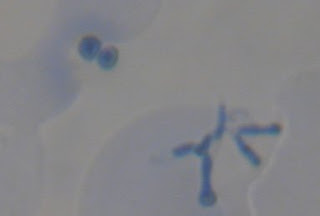

Lesión (mancha blanca) y carie cavitada